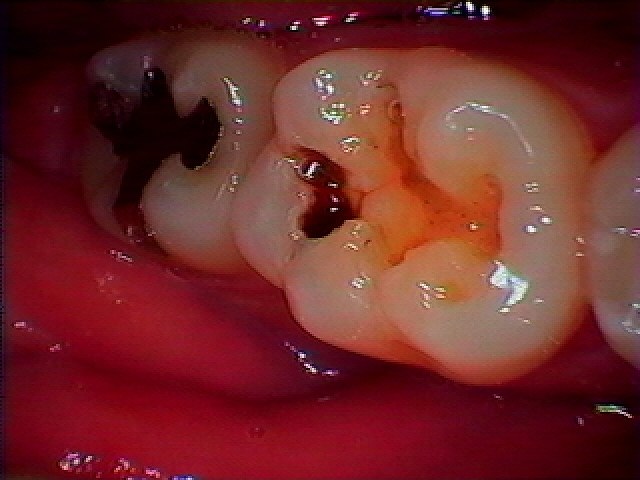

ブログ一覧|広島市安佐南区の歯科医院 ブログ一覧 トップ ブログ一覧 お知らせ スタッフブログ ブログ一覧 お知らせ 2019/11/01 銀歯が外れたので見てほしい 痛みはないが虫歯になっているとのこと お知らせ 2019/11/01 左下6番 銀歯が取れた診てほしい セラミックへの審美修復へ お知らせ 2019/10/31 4本分のジルコニアブリッジを作成していきました どの歯も根の治療から行い、再度破折に対する歯の本数も増やし強度を増しています お知らせ 2019/10/31 左下6番がが破折 ブリッジの場合、歯周病の兼ね合い等も考えると大きく治療しないといけなく大事になることもあります お知らせ 2019/10/30 左上6番被せが土台ごと取れた 診てほしい 根の治療からのジルコニアクラウン連冠にて修復 あらかじめ割れる危険のある歯質を損なった歯は連冠にて破折しにくいような設計にしていきます お知らせ 2019/10/30 治療して何年もたつ被せを外し、白いセラミックへの転換 同じやり変えるならきれいにしたい お知らせ 2019/10/29 左上7番の虫歯治療 同じ治療して被せるなら白いセラミックにてきれいにしたいなー とのこと お知らせ 2019/10/29 銀歯の下には虫歯がはびこっています 被せが外れたりしなければ気が付きにくいのですが、、、気が付いたころにはかなりひどくなっているのが虫歯です << 1 2 3 4 5 … 375 376 377 378 379 … 870 871 872 873 874 >> Web診療予約 初めての方へ 選ばれ続ける理由 院内設備について 歯が痛いしみる一般歯科 歯がぐらぐらする歯周病 健康な歯を保ちたい予防歯科 子供の虫歯予防をしたい小児歯科 銀歯をセラミックに審美歯科 白い歯を目指しませんか?ホワイトニング 矯正専門医がいるので安心矯正歯科 抜けた歯を補いたいインプラント・入れ歯 医院案内 スタッフ紹介 メリィハウス歯科クリニックオフィシャルホームページ ラベンダー歯科クリニックオフィシャルホームページ お知らせ・ブログ ホーム 診療科目 一般歯科 歯周病治療 予防治療 小児歯科 審美治療 ホワイトニング 矯正歯科 入れ歯・インプラント マウスピース矯正 初めての方へ 院長・スタッフ 設備紹介 医院案内・アクセス メニューを閉じる